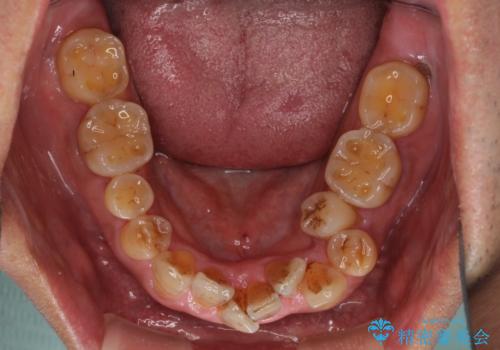

- 骨格的な咬み合わせのズレ、前歯のデコボコとクロスバイトを気にして来院された患者様です。

全額的にデコボコが強いため、上下左右の小臼歯計4歯を抜歯し、ワイヤー装置による矯正治療を行うこととしました。

抜歯する歯の一部をセオリーである第一小臼歯ではなく、第二小臼歯にすることで、骨格的なずれをカバーするように計画しました。

小臼歯の抜歯する部位を選択したことで、安定した咬み合わせとなりましたが、第二小臼歯を抜歯した部分はスペースを閉じるのに長い期間を要しました。